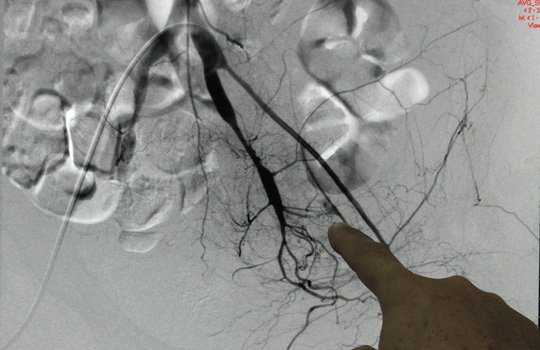

Kỳ lạ ca bệnh chảy máu không cầm

Các bác sĩ vừa Bệnh viện Nhân dân 115 TP HCM vừa "đau đầu" khi xử trí ca bệnh chảy máu dữ dội không rõ...